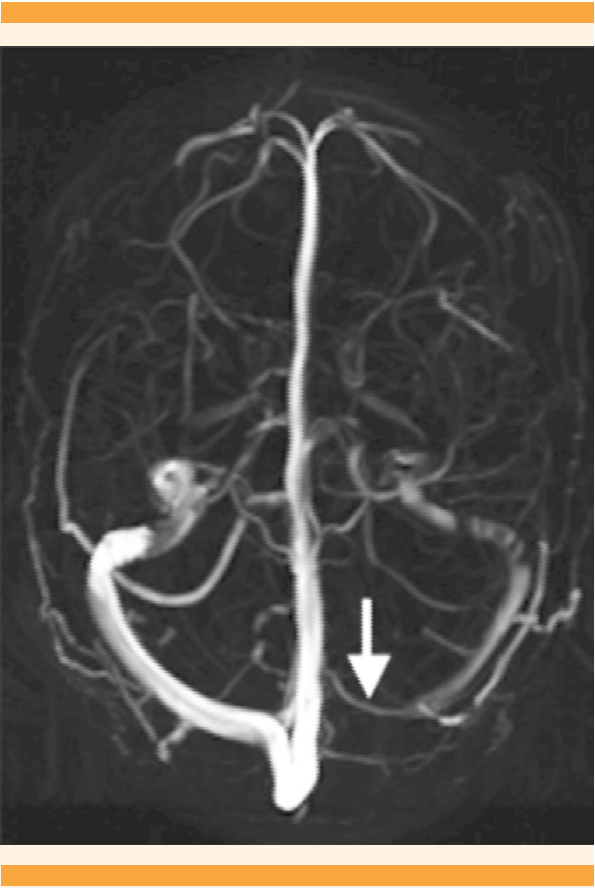

La resonancia magnética, en venorresonancia, mostró: trombosis en el primer tercio del seno lateral transverso izquierdo (Figura 1). Se indicó tratamiento anticoagulante con enoxaparina, a dosis terapéuticas y 2 mg/día de acenocumarol por vía oral. Dos días después del inicio de los anticoagulantes los controles bioquímicos mostraron: prolongación del International Normalized Ratio (INR) (1.66, 0.8-1.2) y TP (20.7, 11.1-16). La paciente permaneció estable en las cifras tensionales y la cefalea fue disminuyendo gradualmente, hasta encontrarse asintomática. Se dio de alta por mejoría y con un puntaje en la escala de Rankin modificada2 de 0 (Cuadro 2). El quinto día de estancia intrahospitalaria, décimo tercero del puerperio, recibió nifedipino de liberación prolongada a la dosis de 60 mg/día, 100 mg/día de metoprolol y 2 mg/día de acenocumarol por vía oral.

Figura 1 Resonancia magnética en secuencia cefálica, en plano axial, que muestra la ausencia de flujo sanguíneo en el seno transverso lateral izquierdo (flecha) ocasionado por el tromboembolismo venoso.